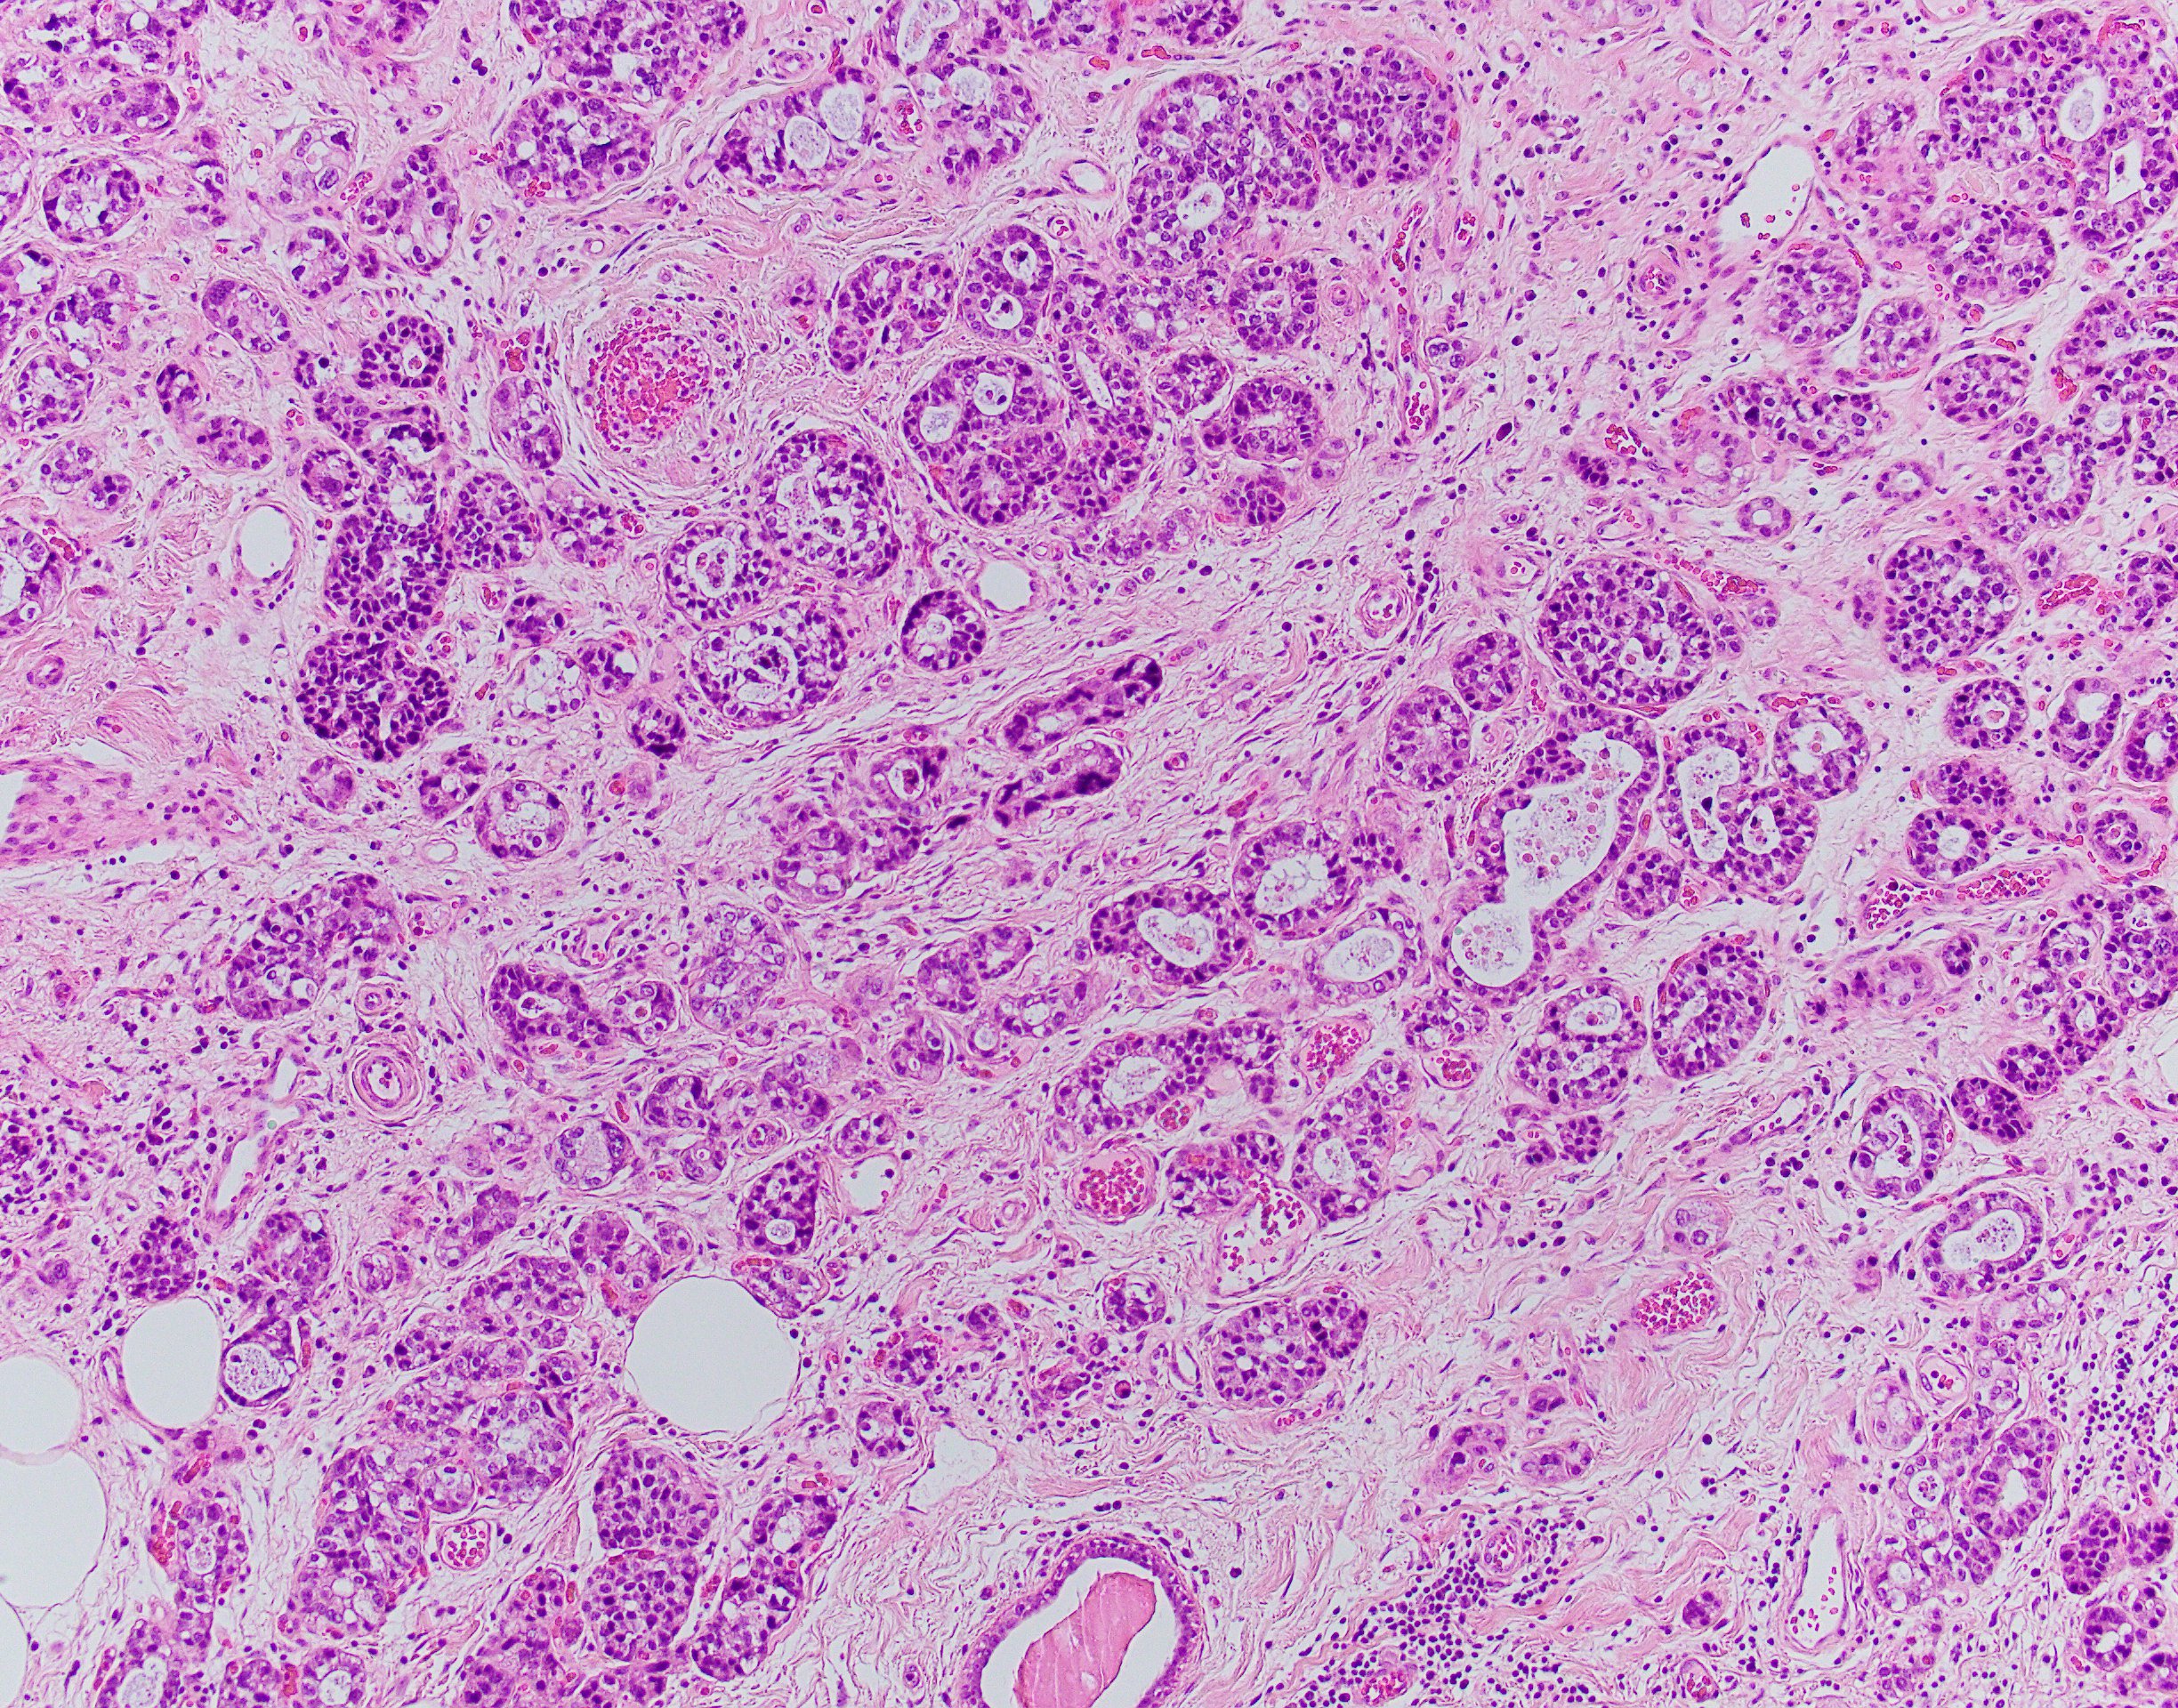

Acinic cell carcinoma (ACC) is a rare histological type of malignant epithelial neoplasms characterized by widespread acinar cell-like differentiation.

The ACC of the breast was first described in 1996 by Roncaroli et al. The histological pattern of these cases is predominantly solid with a microglandular structure, with associated cystic or/and papillary components.

ACC is characterized by serous acinar differentiation with zymogen-type cytoplasmic granules. The immunohistochemical profile of breast Acinic cell carcinoma shares many features with Acinic cell carcinoma of the salivary glands, with frequent expression of GCDFP-15, S-100, and a-1-Antichymotrypsin, as well as PAS-D positivity.

The differential diagnosis are microglandular adenosis and granular cell carcinomas (apocrine carcinomas, secretory carcinoma, oncocytomas and neuroendocrine carcinomas)